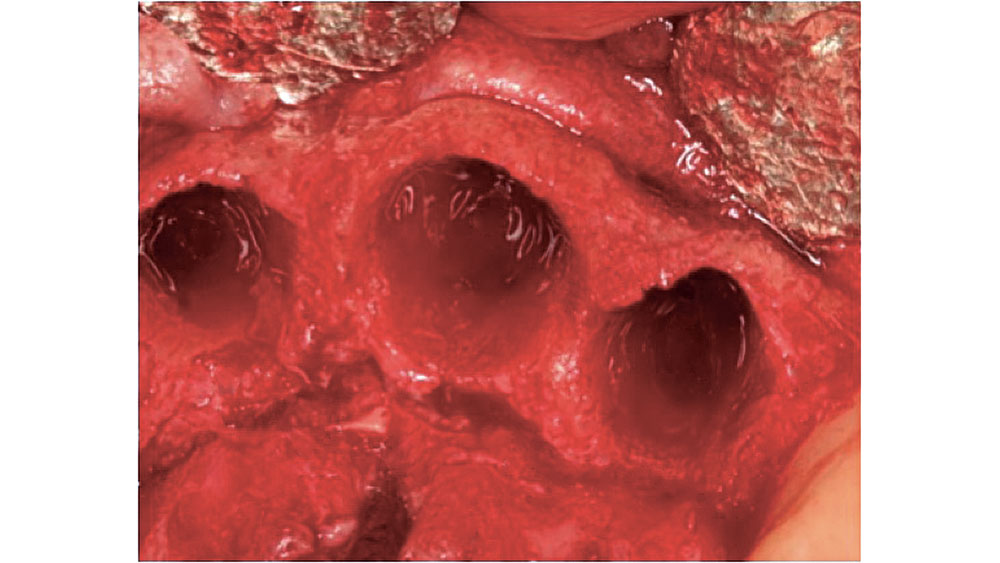

FOUR-WALLED EXTRACTION SOCKET

With a four-walled extraction socket, one wall is missing — typically the buccal or facial plate (Fig. 4). Unlike a five-walled socket, which heals through bone regeneration, a four-walled socket will most likely heal via bone repair, compromising the predictability of the bone healing process (Figs. 5a, 5b). When the buccal wall is missing, many required elements of the bone regeneration process are lost. The loss of the buccal wall will reduce the ability of the space to be maintained. Because space maintenance is required for predictable bone growth, an increased amount of bone loss most likely will occur, along with a decrease in host-bone vascularization. This may lead to reduced blood supply for bone formation and bone growth factors entering the site.

In four-walled extraction sockets, grafting is indicated to reduce residual bone and soft-tissue loss. The maxillary anterior region may resorb up to 23 percent in the first six months after an extraction, and an additional 11 percent over the following five years.4 Within 24 months, an average of 40 to 60 percent of the preexisting height and width of bone may be lost with this type of extraction socket.5